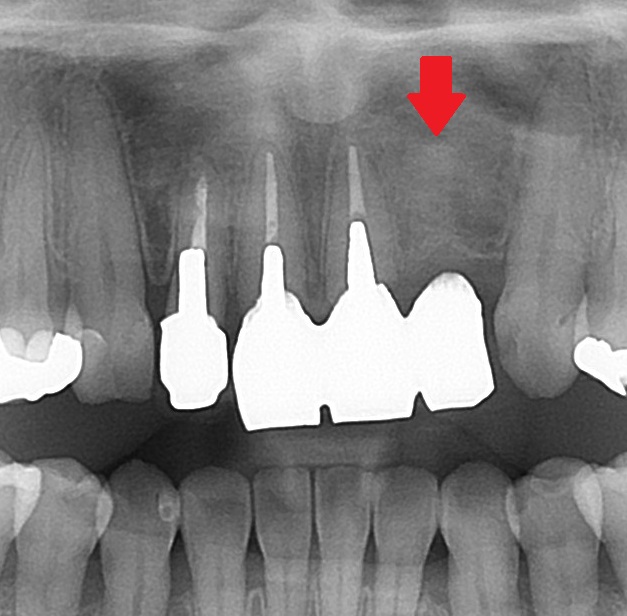

エックス線を見てみると

こちらの矢印の歯のコアが、太く、適正な方向に入っていないためです。方向がそれています。

斜めに埋め込まれてしまっており、赤い矢印の部分の歯の残量が無いためです。既に穴が開いているかもしれません。

このコアを外す際に、赤い矢印の箇所に穴が開くか、割れる可能性があります。

現在、歯に症状が無いために、このまま現状を維持することを患者さんと相談しました。